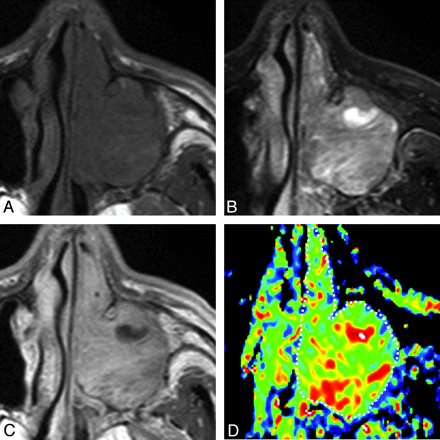

A 46-year-old man with rhinosinusitis. A, Axial T1-weighted MR image (TR/TE = 500/15 ms) shows the left maxillary sinus filled with homogeneous inflammatory tissues. B, Axial FS (SPAIR) T2-weighted MR image (TR/TE = 6385/80 ms) shows the left maxillary sinus filled with heterogeneous inflammatory tissues. C, Axial contrast-enhanced T1-weighted MR image (TR/TE = 500/15 ms) shows heterogeneously enhanced tissue in the left maxillary sinus. D, Axial color ADC map shows high ADC areas in the lesion periphery. Overall ADC = 2.0 × 10−3 mm2/s. Areas with extremely low, low, intermediate, and high ADCs occupy 2%, 8%, 24%, and 66%, respectively, of the lesion.